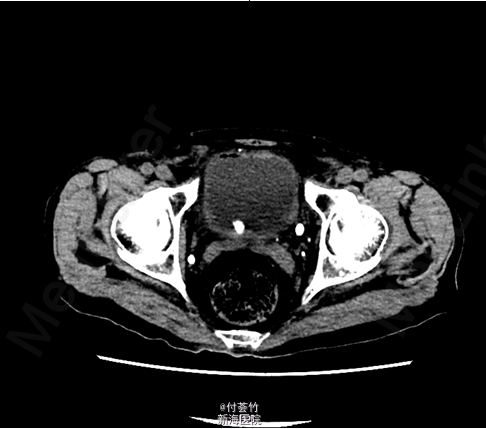

双肾区无红肿、隆起,无叩痛,双侧肋脊点、肋腰点无压痛。腹平软,双侧上中输尿管点无压痛,膀胱区无压痛。双侧腹股沟区未触及肿物 入院后查双肾CTU:膀胱结石,慢性膀胱炎,膀胱少许积气;左肾下部病灶,考虑良性病变,复杂囊肿可能大;双肾多发囊肿;前列腺电切术后改变,残留前列腺钙化